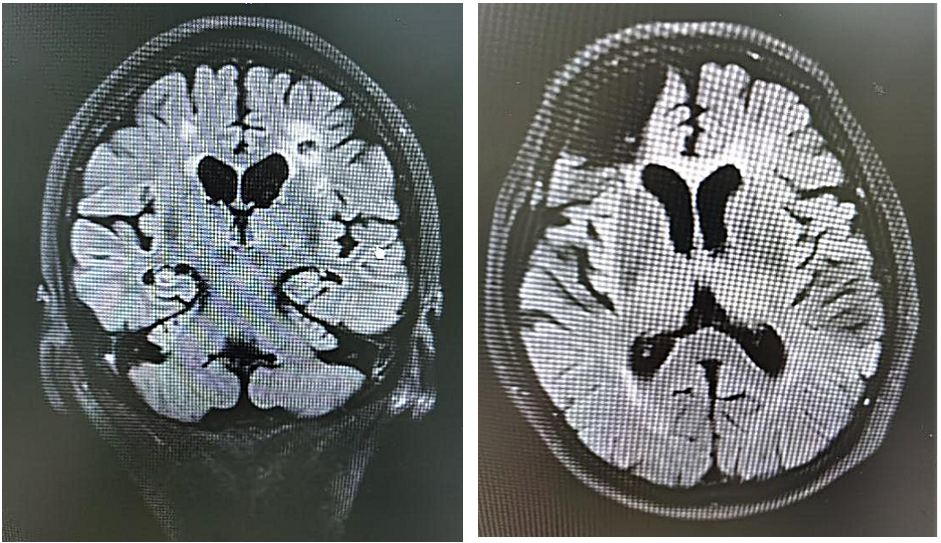

后来,家人带她到医院就诊。赵阿姨的MRI显示有脑梗,同时也有脑萎缩,海马萎缩已经II级。

图/赵阿姨头颅MRI

但赵阿姨记性变差,脑部MRI显示海马有萎缩的情况,则是我携手“夫君”阿尔茨海默病共同造成的。